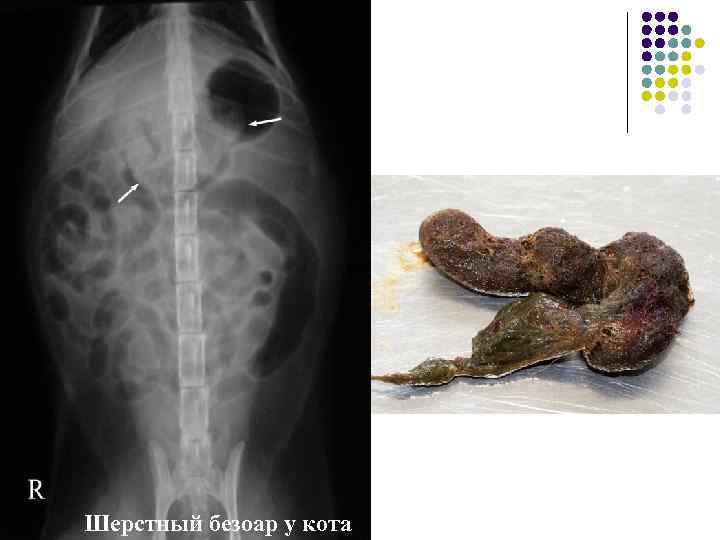

Инородные тела в желудке Шерстный безоар у кота

Кишечная непроходимость Шерстный безоар у кота